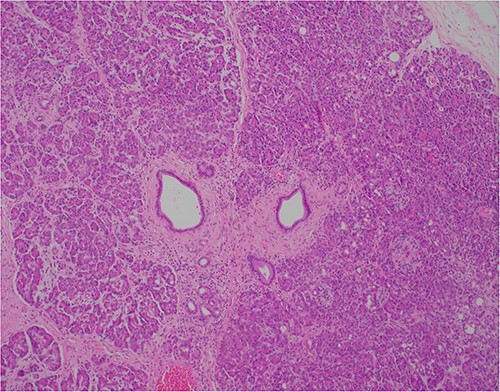

At outpatient phone clinic review 2 months post-surgery, the patient had recovered well, and his pre-operative symptoms of nausea, vomiting and pain had completely resolved. The histopathology of the gallbladder found chronic cholecystitis with cholelithiasis, in addition to a 6 mm focus of pancreatic heterotopia in the gallbladder wall. This heterotopic tissue contained acini, ducts and islet cells, classifying it as Type I pancreatic heterotopia (Figs 1–3).

×20 objective lens; normal duct towards left hand side; acini (with dense pink cytoplasmic granules) and islets (clusters of pale cells).